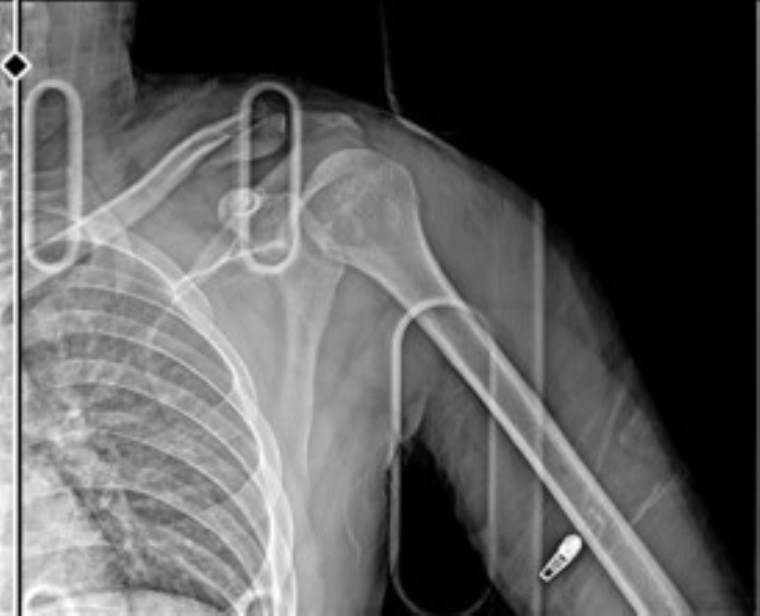

KOLUNDA KALICI HASAR OLUŞTU

Çiçek, yaralı halde hastaneye kaldırılırken, sağ omzundan ameliyat oldu. Çiçek'in platin takılan kolunda kalıcı hasar oluştu.